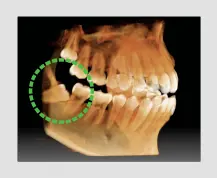

The FOV of the A9 provides an arch-shaped volume, anatomically 9.3X8, showing a wider view of dentition when compared to other devices with the same 8X8 FOV. When the tooth is lying on its side, there is a high possibility that the tooth will be cut out of the image. This possibility is eliminated with our "arch-shaped volume" and shows the hidden dentition area.